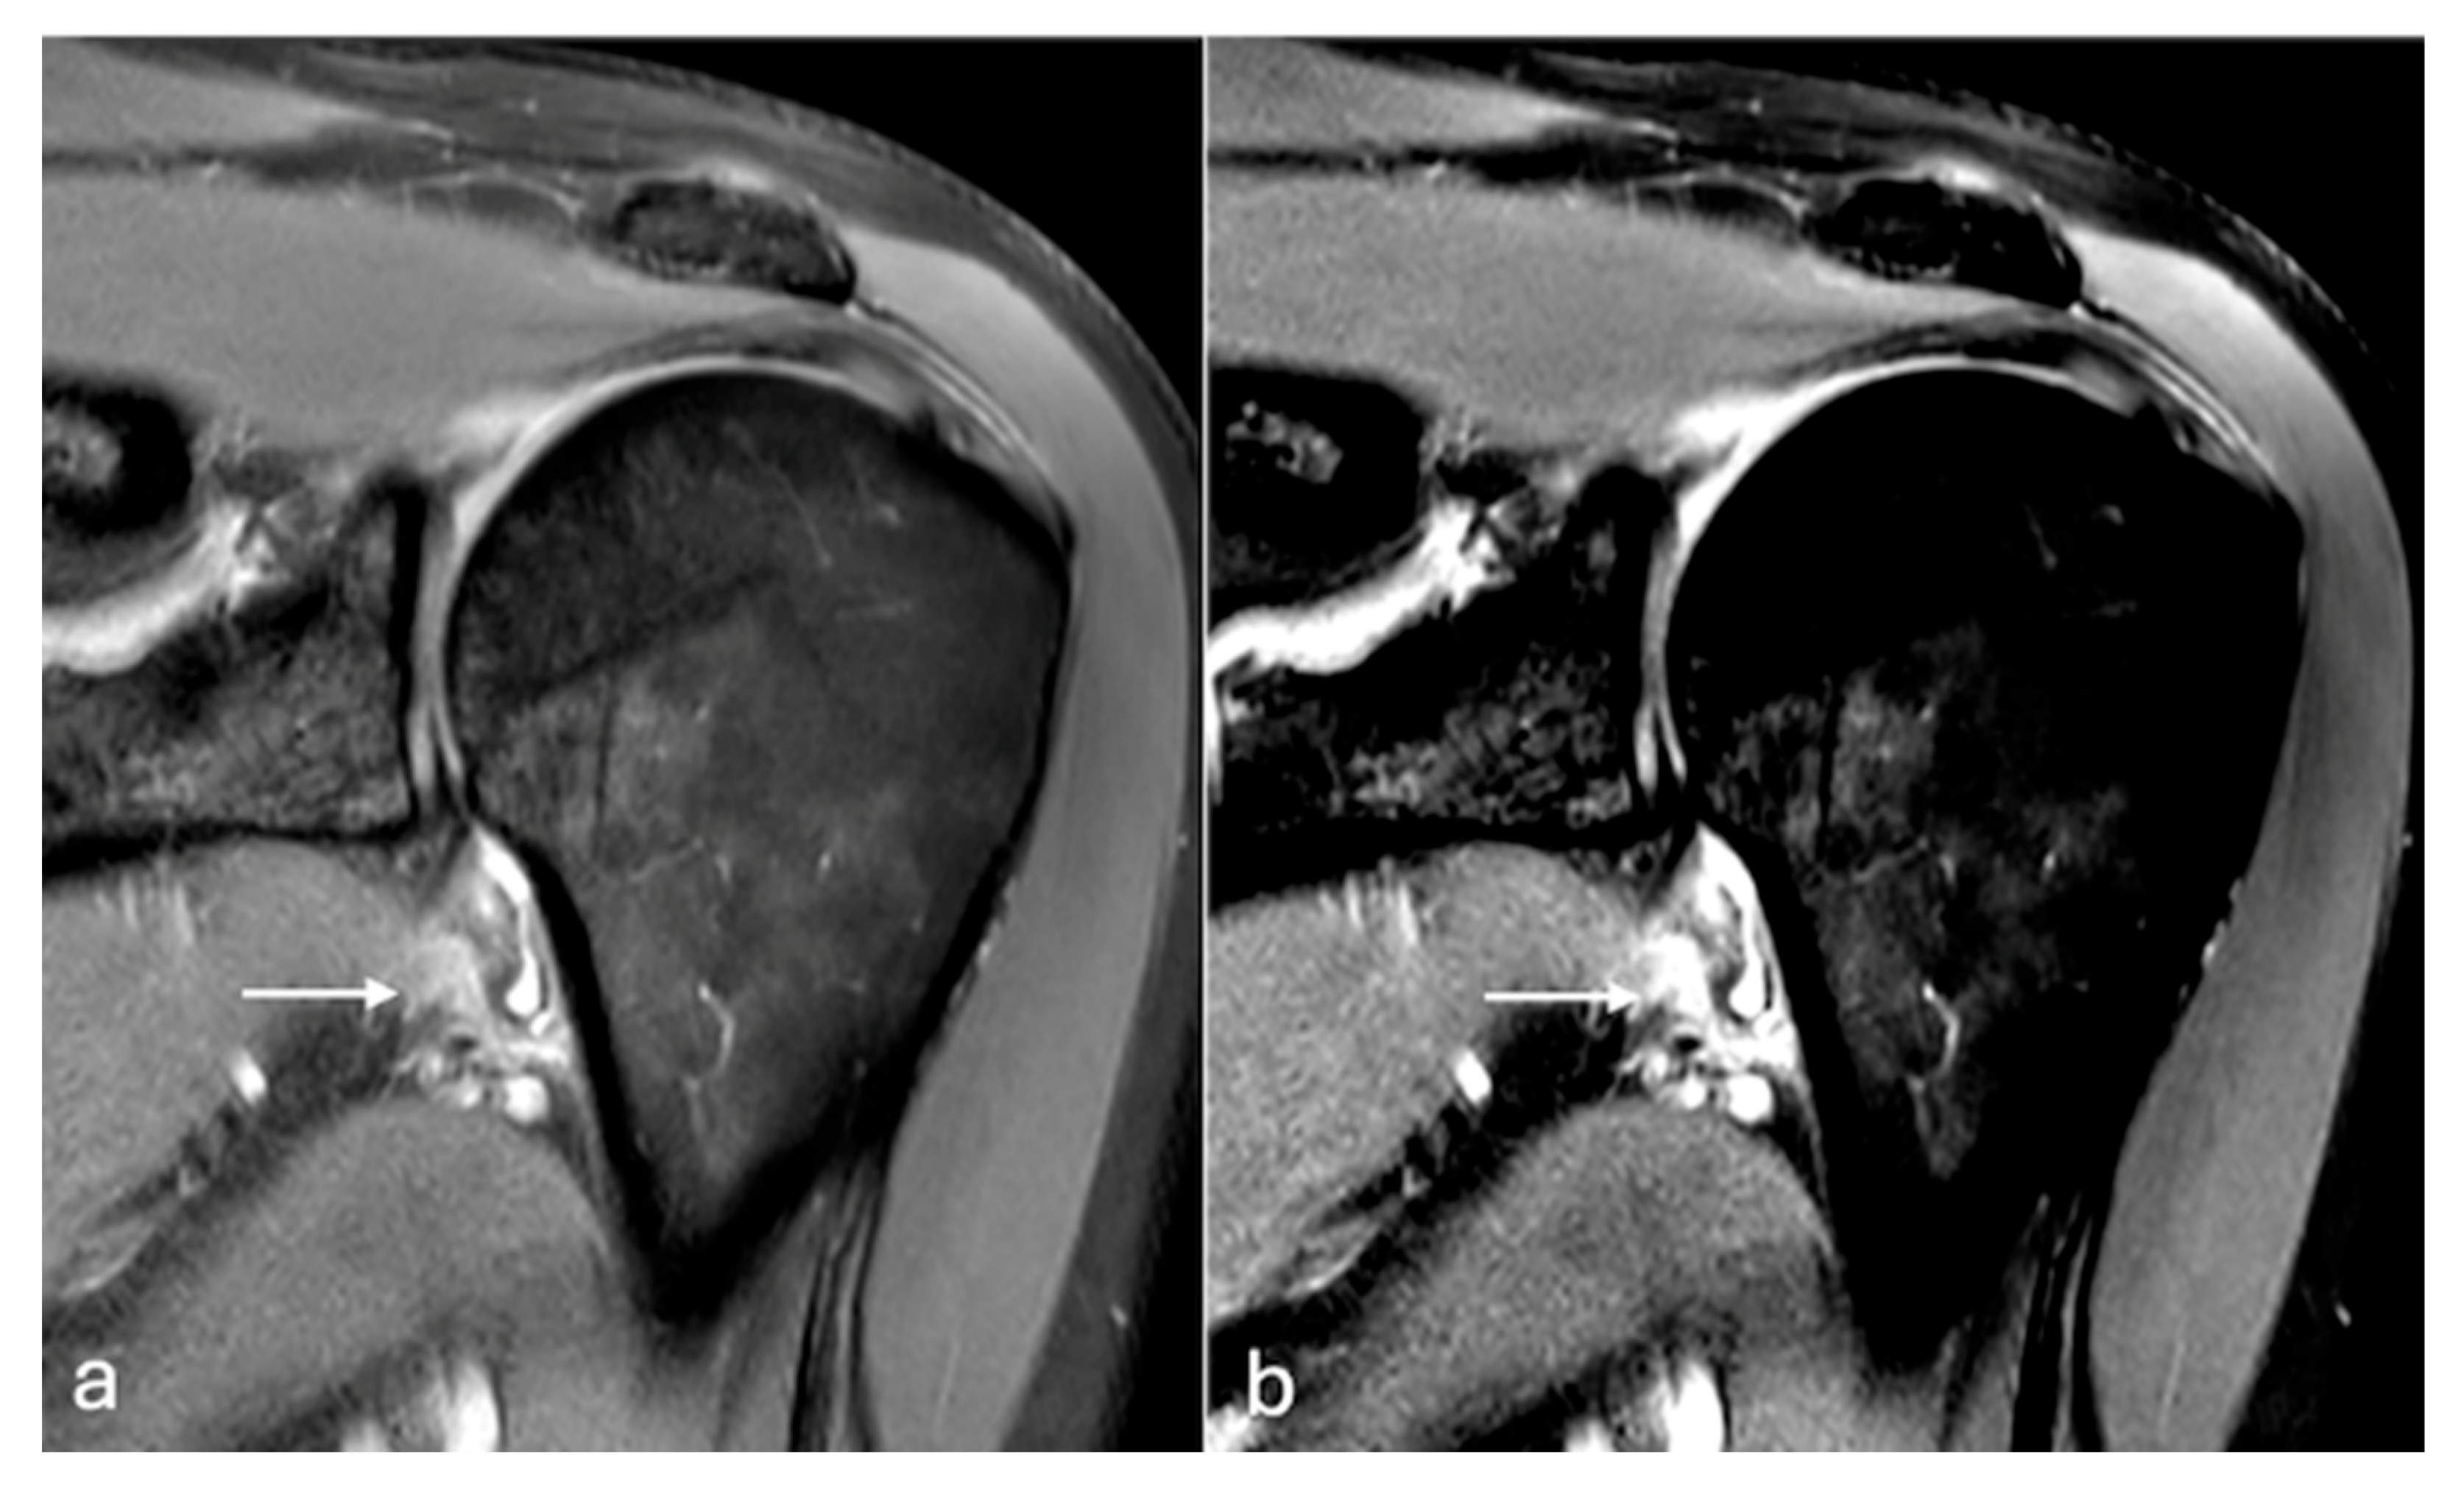

Figure 6. PDFS sagittal images of chest wall (a,b). Soft tissue oedema changes seen in intercostal muscle (arrow) are better delineated with modified windowing (b) in comparison to the default window (a). W/L of image (a)—1704/961, (b)—932/956.